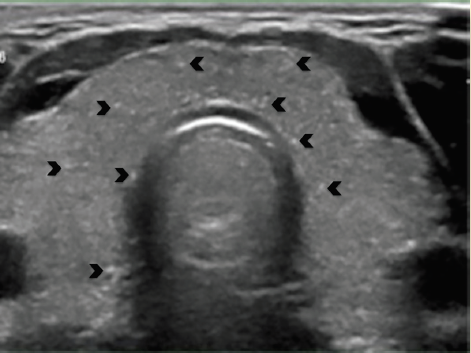

En el US de cuello la glándula tiroides es de situación normal y sus bordes son regulares y bien definidos, el lóbulo derecho tiene medidas de 16 × 13 × 41 mm en sus ejes anteroposterior, transversal y longitudinal respectivamente, el lóbulo izquierdo mide 16 × 16 × 47 mm en los mismos ejes, con un volumen tiroideo total de 10.6 ml, en el parénquima tiroideo del lóbulo izquierdo se identifica una imagen nodular sólida, hipoecoica (figura 2), más ancha que alta, de bordes mal definidos y sin extensión extratiroidea, con múltiples ecos puntiformes en su interior y con diámetro máximo de 6 mm, el cual se clasifica como TI-RADS 5 según los criterios del Colegio Americano de Radiología (ACR)5. También se identificaron múltiples ecos puntiformes de distribución difusa en ambos lóbulos tiroideos (figura 3), el resto del parénquima se observa sin alteraciones.

Figura 3 Ecos puntiformes de distribución difusa en un parénquima tiroideo normal (puntas de flecha).